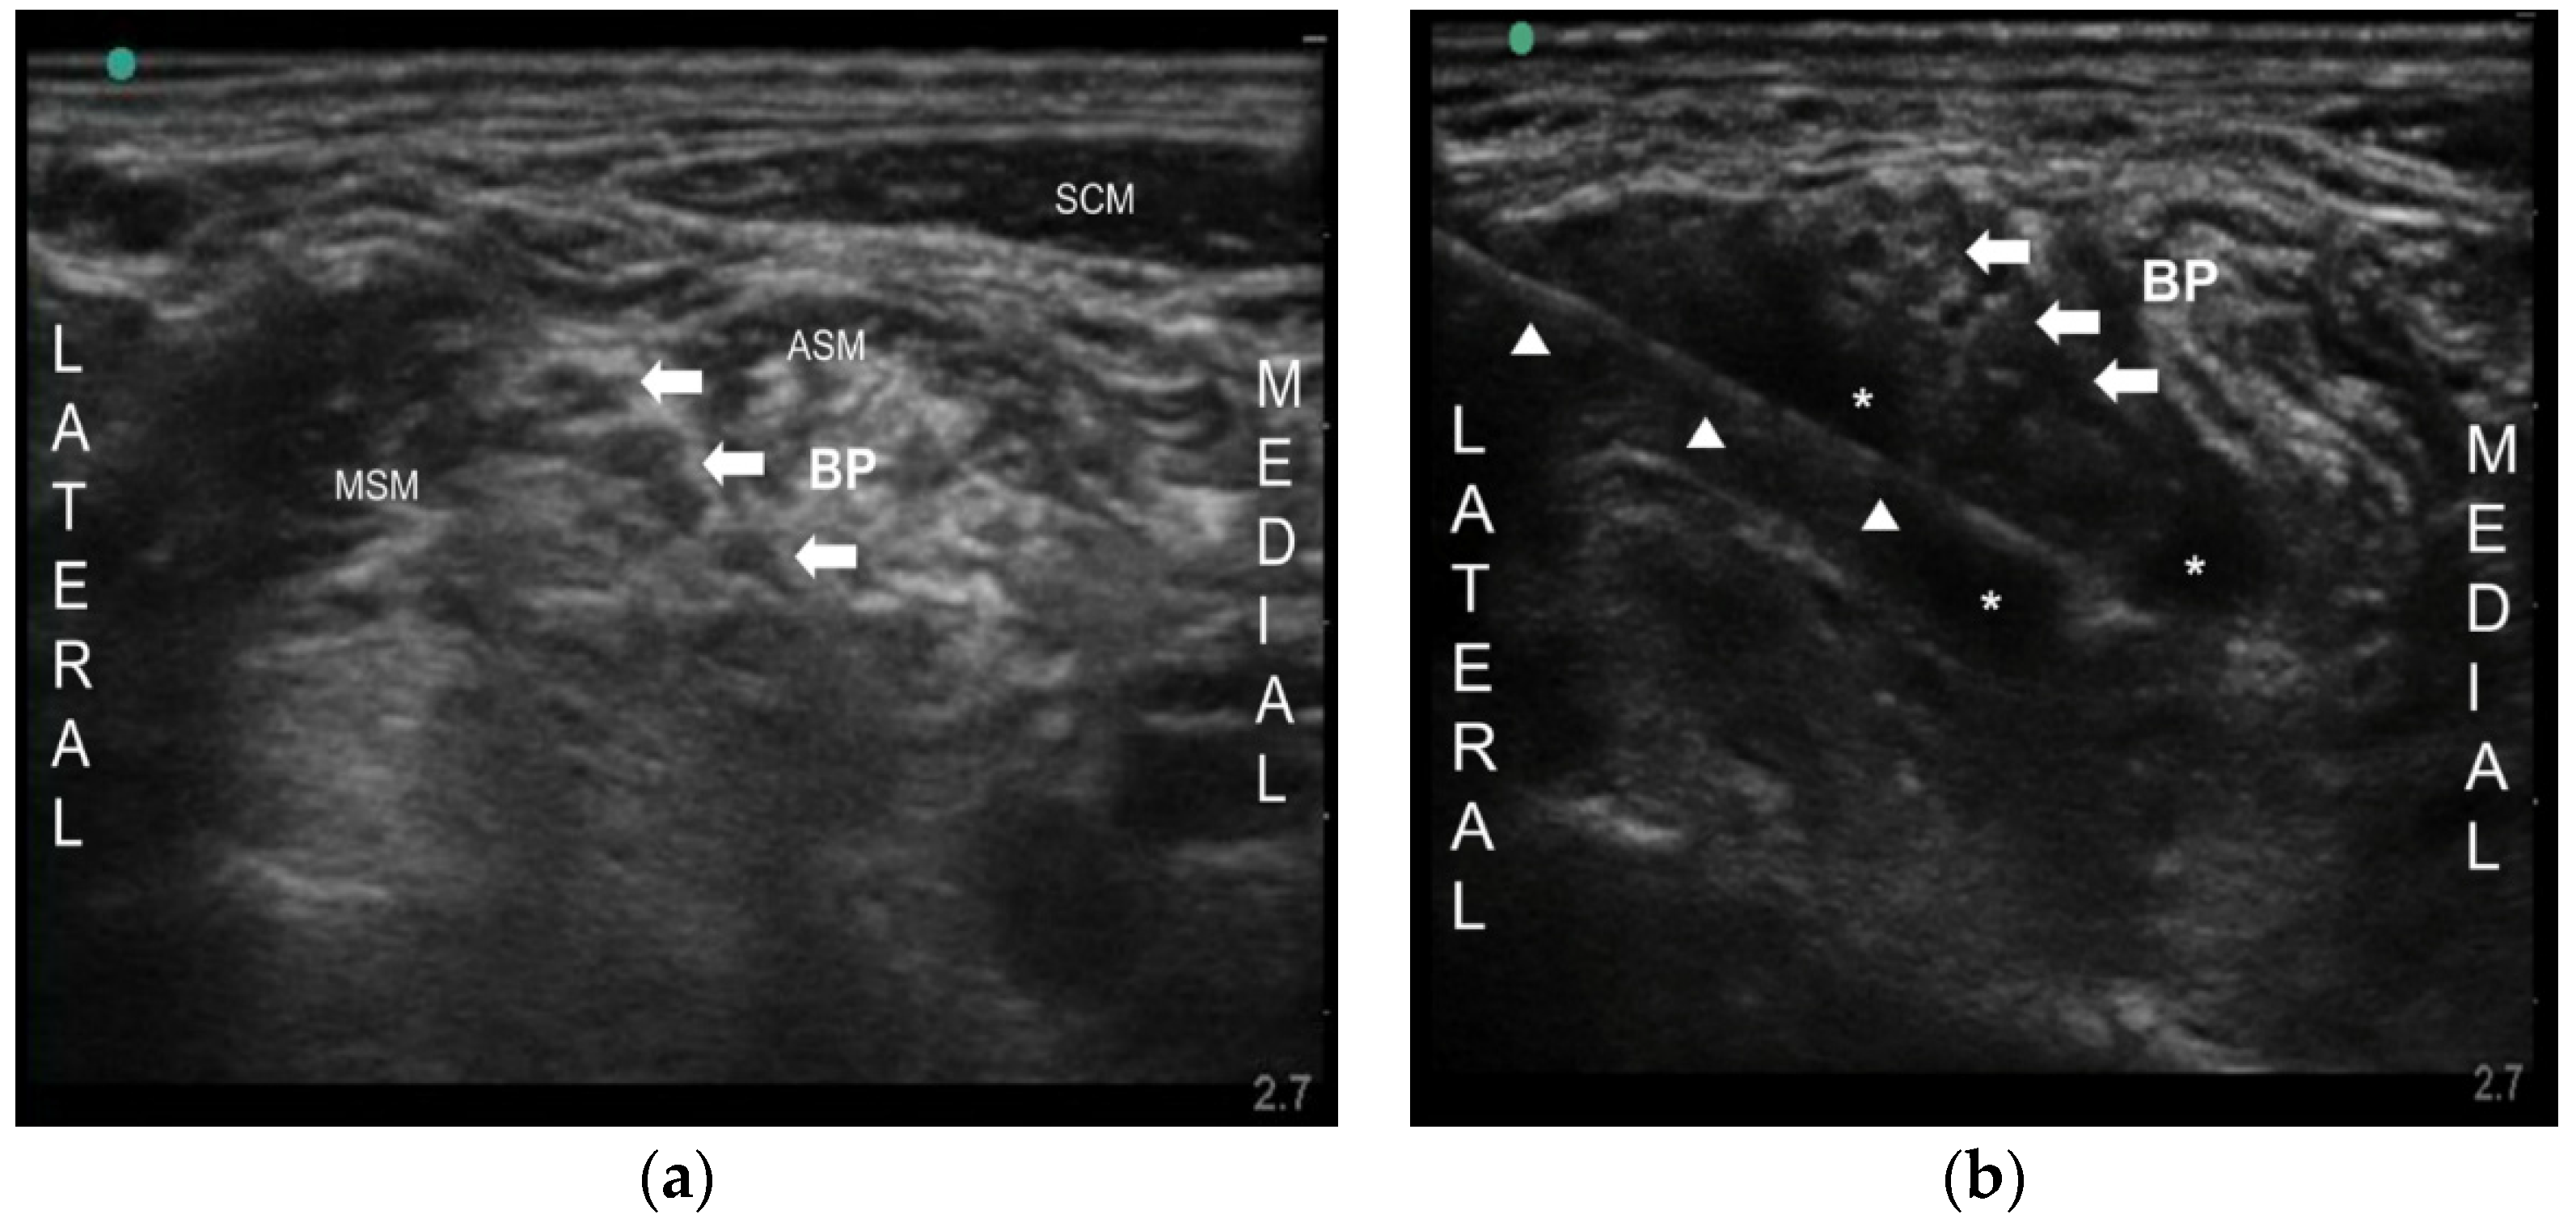

Figure 1.

(a) Ultrasound image of the brachial plexus between the anterior and middle scalene muscle. Arrows indicate brachial plexus (BP); (b) Ultrasound image of spreading the drugs around the brachial plexus. Arrowheads indicate the needle. Arrows indicate BP. ASM anterior scalene muscle, MSM middle scalene muscle, SCM sternocleidomastoid muscle, * injected drug surrounding the BP.

A 63-year-old woman was referred to our pain clinic with PHN for one year. She was an acute myelogenous leukemia patient and had undergone allogeneic peripheral blood stem cell transplantation in the preceding year. She was a terminal cancer patient. Three months after herpes zoster from left shoulder to all fingers, she was diagnosed as PHN by dermatologist. She complained of a very sharp and burning pain on a whole left arm (from shoulder to all fingers, C5–8 dermatome). Hyperalgesia, tactile allodynia, and paresthesia were accompanied. Her visual analog scale (VAS) was 9/10. She was prescribed tacrolimus 0.5 mg/day for immunosuppression, neurontin 600 mg/day, nortriptyline 10 mg/day, and fentanyl patch 12 μg for PHN. Nonetheless, her pain was not controlled by medication (VAS 8/10). Loading neurontin 900 mg/day was attempted, but failed due to severe nausea and vomiting. She was consulted by a gastroenterologist because of poor oral intake with a cachexic condition and gastrointestinal distress. An ultrasound-guided brachial plexus block (BPB) was attempted. After sterilization, a high frequency linear transducer was positioned in the transverse plane to identify the scalene muscles and the brachial plexus that is sandwiched between the anterior and middle scalene muscles. The needle (BD, Singapore, Singapore, 50 mm 25G) was inserted in-plane into the interscalene groove between the anterior and middle scalene muscles using 10 mL of 0.4% lidocaine (Figure 1). The VAS decreased from 8/10 to 3–4/10 for only 3 days. Then, cervical epidural block (C6–7 level, left side) with 4 mL of 0.4% lidocaine and 1 mg of dexamethasone was performed under fluoroscopy. Her pain was relieved (VAS from 8/10 to 2–3/10) just for a week. Therefore, after obtaining patient’s consent form and institutional review board approval (KC13ZISE0739), we injected 10 mL of 0.1% bupivacaine with 50 Botox units (BOTOX®, Allergan Inc., Irvine, CA, USA) around brachial plexus. Since 50 Botox units were reconstituted in 2 mL of 0.9% normal saline, total volume injected was 12 mL (Figure 1). Subsequently, the VAS was reduced from 8/10 to 2–3/10, and at the five-month follow-up, her pain was well controlled (VAS 3/10) and she was satisfied with BoNT-A treatment.